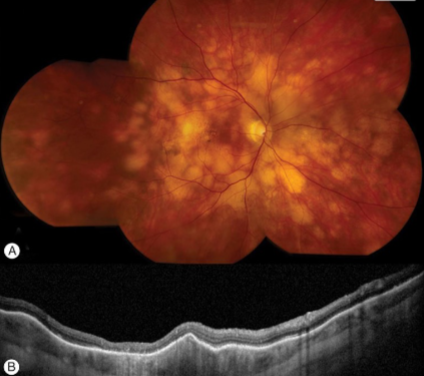

metastatic carcinoma

metastatic carcinoma

metastatic carcinoma

metastatic carcinoma

metastatic carcinoma

metastatic carcinoma

metastatic carcinoma

metastatic carcinoma

metastatic carcinoma